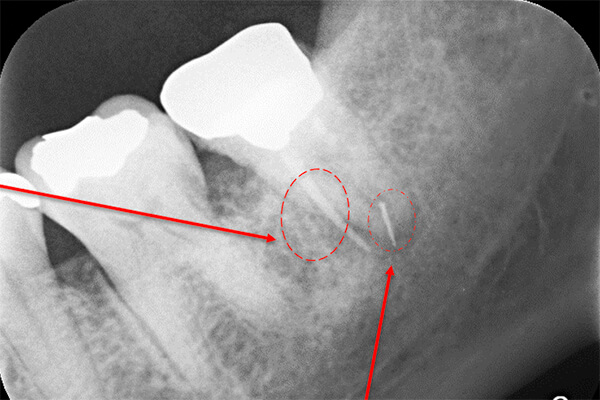

根の横に誤った穴をあけてしまい、気づかずに薬を入れてしまっている。また、器具が破折し、根の先に飛び出ている。

更に、拡大すると歯根破折に加え、器具の破折片も確認できる。